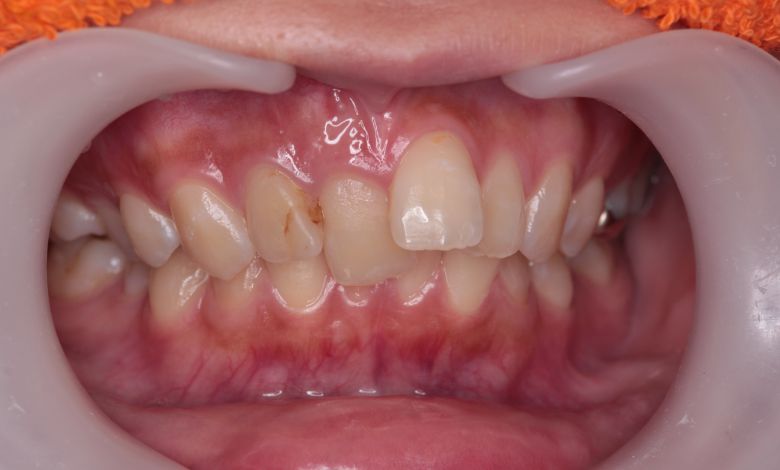

上下ともに歯並びが乱れており、噛み合わせにも大きな不調和が見られる

他院にて上下左右4本の抜歯を前提とした矯正治療を提案されていました。上顎・下顎ともに歯列弓が狭く、

V字型の弓状を呈していたため、叢生(歯の重なり)が強く、噛み合わせにも不調和が見られる状態でした。

上下の咬合関係も不正で、機能的にも審美的にも問題のある状態でした

上下の前歯に強い重なりが見られます。特に上顎犬歯と下顎前歯のズレが顕著で、自然な咬合が形成されていない